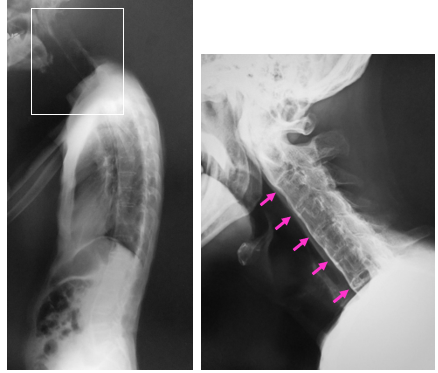

図 (左)背骨を横からみたX線です。背骨がすべて骨癒合しています。

(右)左の写真の四角の部分(頚椎)のX線です。全ての頚椎がくっついています。